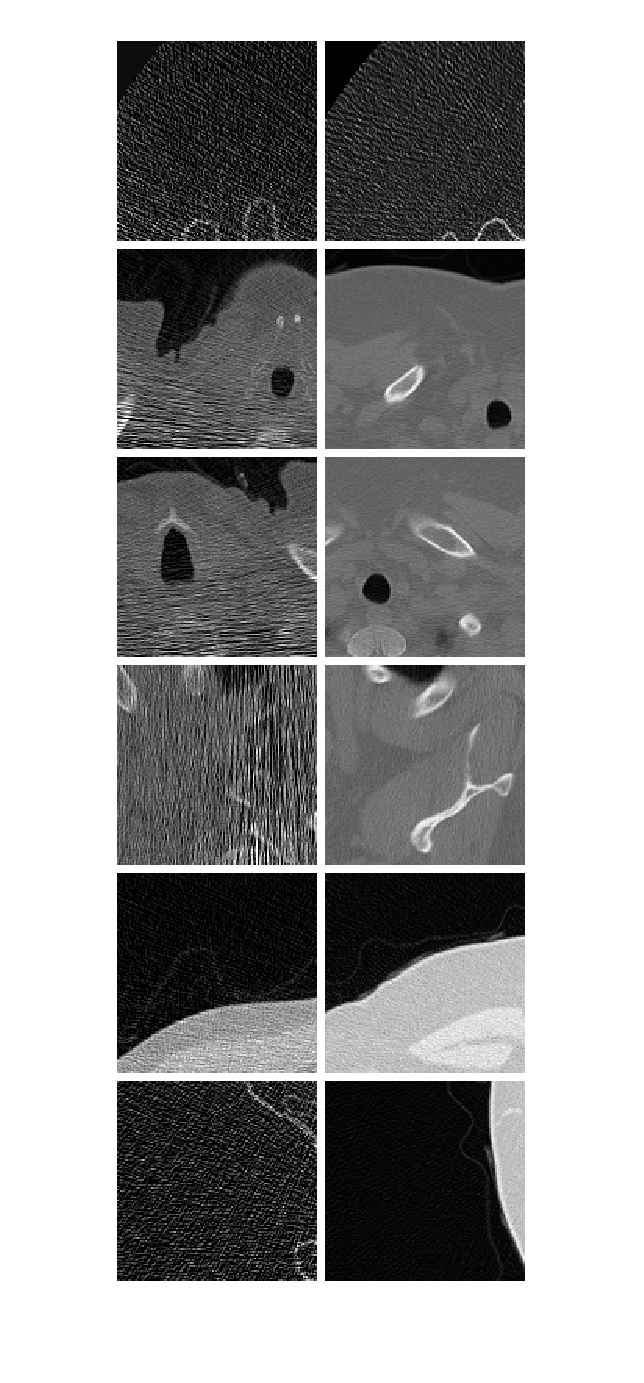

Посмотрите на некоторых низкая доза и пары закрашенной фигуры большей дозы изображений от набора обучающих данных. Заметьте, что пары изображений низкой дозы (слева) и большей дозы (справа) отображают, являются непарными, как они от различных пациентов.

numImagePairs = 6; imagePairsTrain = []; for i = 1:numImagePairs imLowAndHighDose = read(dsTrain); inputImage = imLowAndHighDose.InputImage{1}; inputImage = rescale(im2single(inputImage)); responseImage = imLowAndHighDose.ResponseImage{1}; responseImage = rescale(im2single(responseImage)); imagePairsTrain = cat(4,imagePairsTrain,inputImage,responseImage); end montage(imagePairsTrain,Size=[numImagePairs 2],BorderSize=4,BackgroundColor="w")